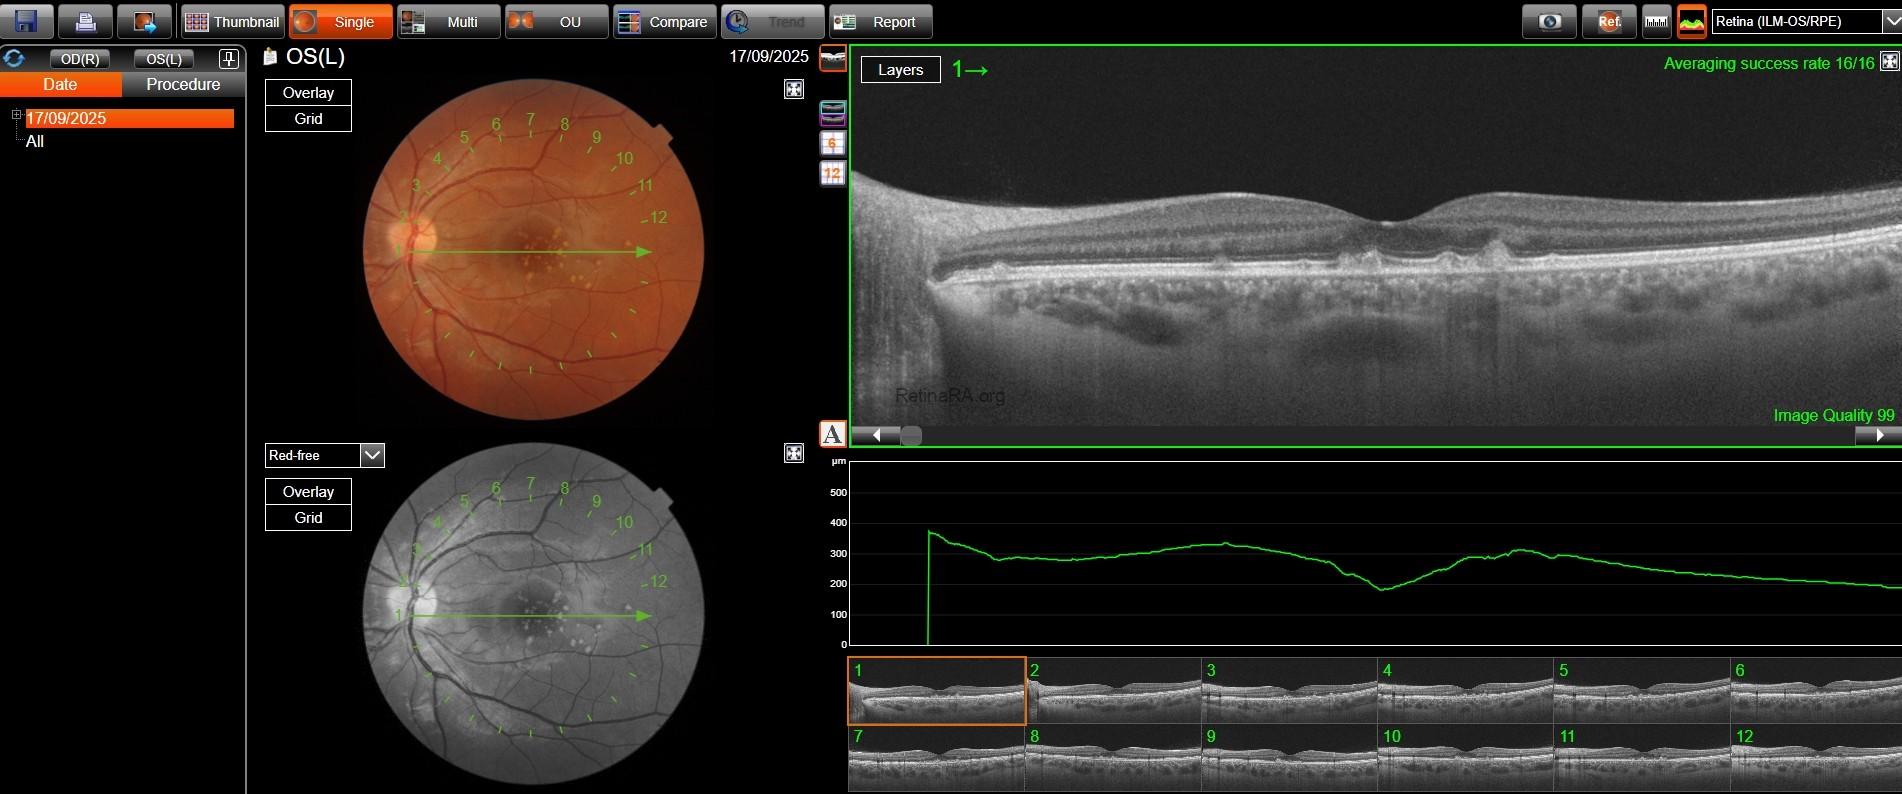

Fundus true-color photo shows multiple large yellowish drusen-like lesions scattered throughout the posterior pole and mainly clustered in the macular region in OU. On FAF, these lesions appear hyperautofluorescent with a surrounding hypoautofluorescent halo.

SD-OCT reveals dome-shaped RPE elevations with internal homogeneous medium reflectivity and increased central backscattering compared to their periphery; their size is variable, with the largest ones even deforming the overlying EZ band and possibly thinning the overlying retinal layers. No RPE and/or outer layer atrophy was found, as well as no subretinal and/or intraretinal fluid. OCT-A was unremarkable OU. En-face OCT segmented shows an hyperreflective center surrounded by a marked hyporeflective ring.

The patient already had an OCT performed in 2023, which showed complete stability of the lesions in both number and size.